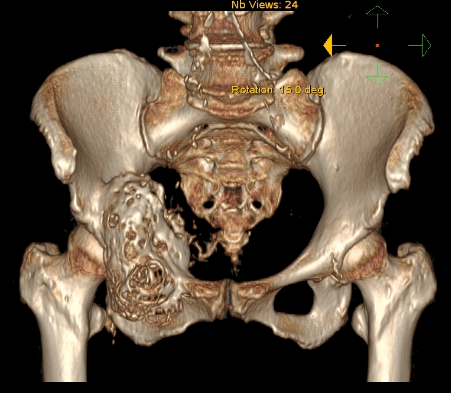

切掉多半骨盆身体掏个大窟窿居然还能到处溜达

骨盆癌